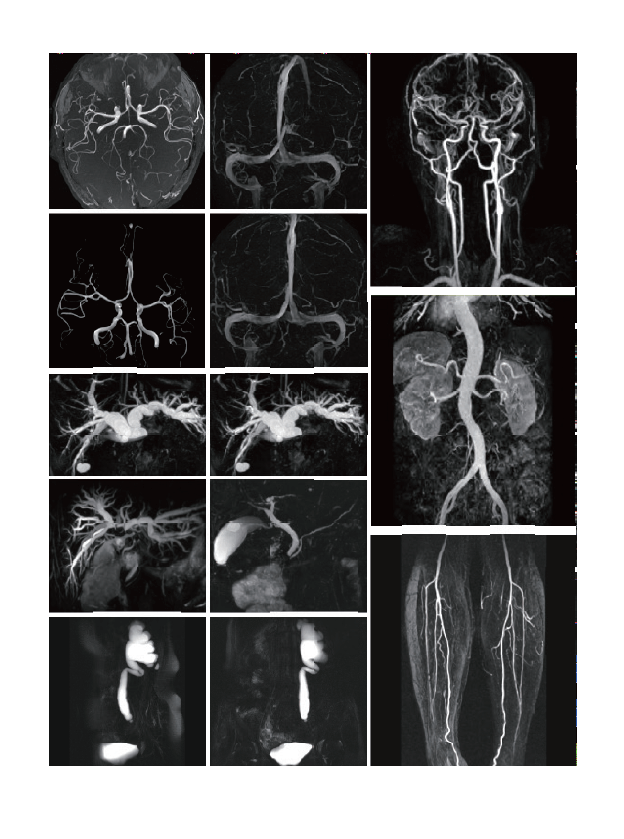

The examination range includes clinical applications such as nerves, blood vessels,abdomen, pelvic cavity, breast, tumor, orthopaedic limb joints, etc.

臨床畫(huà)廊